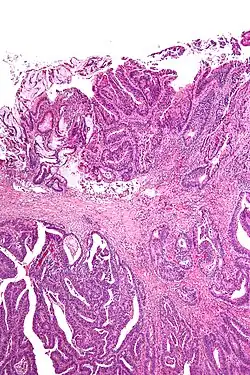

Surgical margin in a surgery report defines the visible margin or free edge of "normal" tissue seen by the surgeon with the naked eye. Surgical margin as read in a pathology report defines the histological measurement of normal or unaffected tissue surrounding the visible tumor under a microscope on a glass mounted histology section.[4][5] A "narrow" surgical margin implies that the tumor exists very close to the surgical margin, and a "wide" surgical margin implies the tumor exists far from the cut edge or the surgical margin. Narrow surgical margin using the bread loafing technique suggests that residual cancer might be left due to false negative error. A surgeon often will perform a second surgery if a narrow surgical margin is noted on a pathology report.